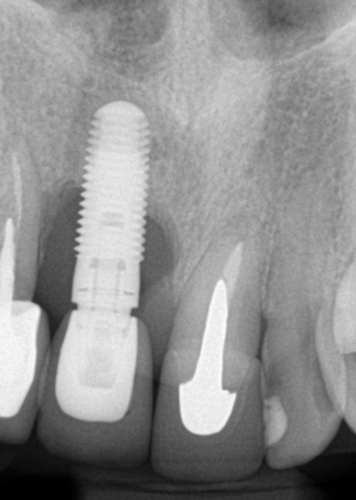

Fig 2. Placement of an implant in a young adult. A female patient had had a congenitally missing maxillary lateral incisor restored when she was 20 years old. Ten years later (Fig 2) the implant-supported restoration was in an infraocclusion state, shorter than the neighboring teeth, due to continuous skeletal growth. Radiograph (Fig 3) showed the marginal bone level of the implant was not affected.

Fig 3. Placement of an implant in a young adult. A female patient had had a congenitally missing maxillary lateral incisor restored when she was 20 years old. Ten years later (Fig 2) the implant-supported restoration was in an infraocclusion state, shorter than the neighboring teeth, due to continuous skeletal growth. Radiograph (Fig 3) showed the marginal bone level of the implant was not affected.

Fig 5. A 35-year-old patient with a missing central incisor due to trauma was restored with an implant (Fig 5, day of second-stage surgery). Twelve years later she presented to the office complaining that pus was draining from the implant and she felt uncomfortable. As can be seen in Fig 6, severe peri-implant bone loss due to peri-implantitis was evident.

Fig 6. A 35-year-old patient with a missing central incisor due to trauma was restored with an implant (Fig 5, day of second-stage surgery). Twelve years later she presented to the office complaining that pus was draining from the implant and she felt uncomfortable. As can be seen in Fig 6, severe peri-implant bone loss due to peri-implantitis was evident.